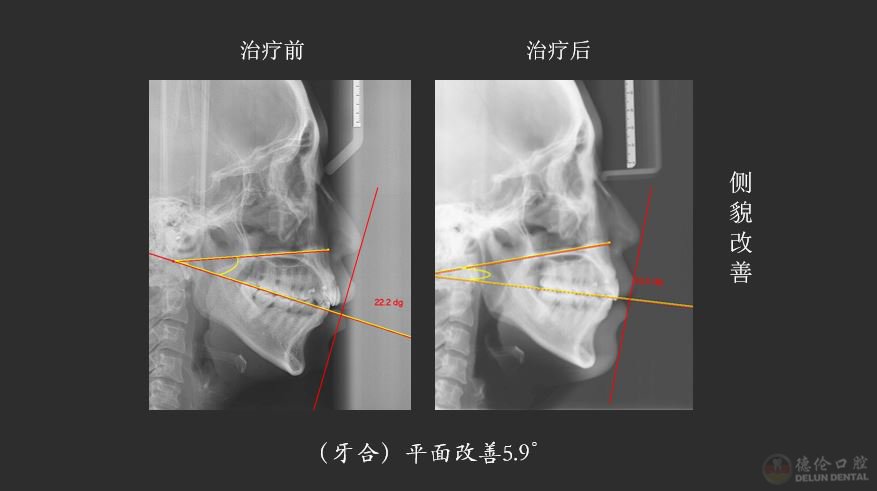

获奖病例侧貌X线前后对比

“按照常规方案,这种情况是不太适合推磨牙远移,因为推磨牙远移会造成整个颌平面的顺时针旋转,就会出现面型更不好看。但是因为给她设计了压低、另外打了支抗钉来控制它的矢状向和垂直向,就没有出现顺时针旋转,反而出现了整个颌平面的逆时针旋转,下巴还变好看了。”熊小琴主任在接受访问时解释道,此案例的难点在于垂直向控制,在没有给患者进行手术的情况下解决了患者主诉、满足了个性化要求,矫牙结束后患者自己感觉很满意。